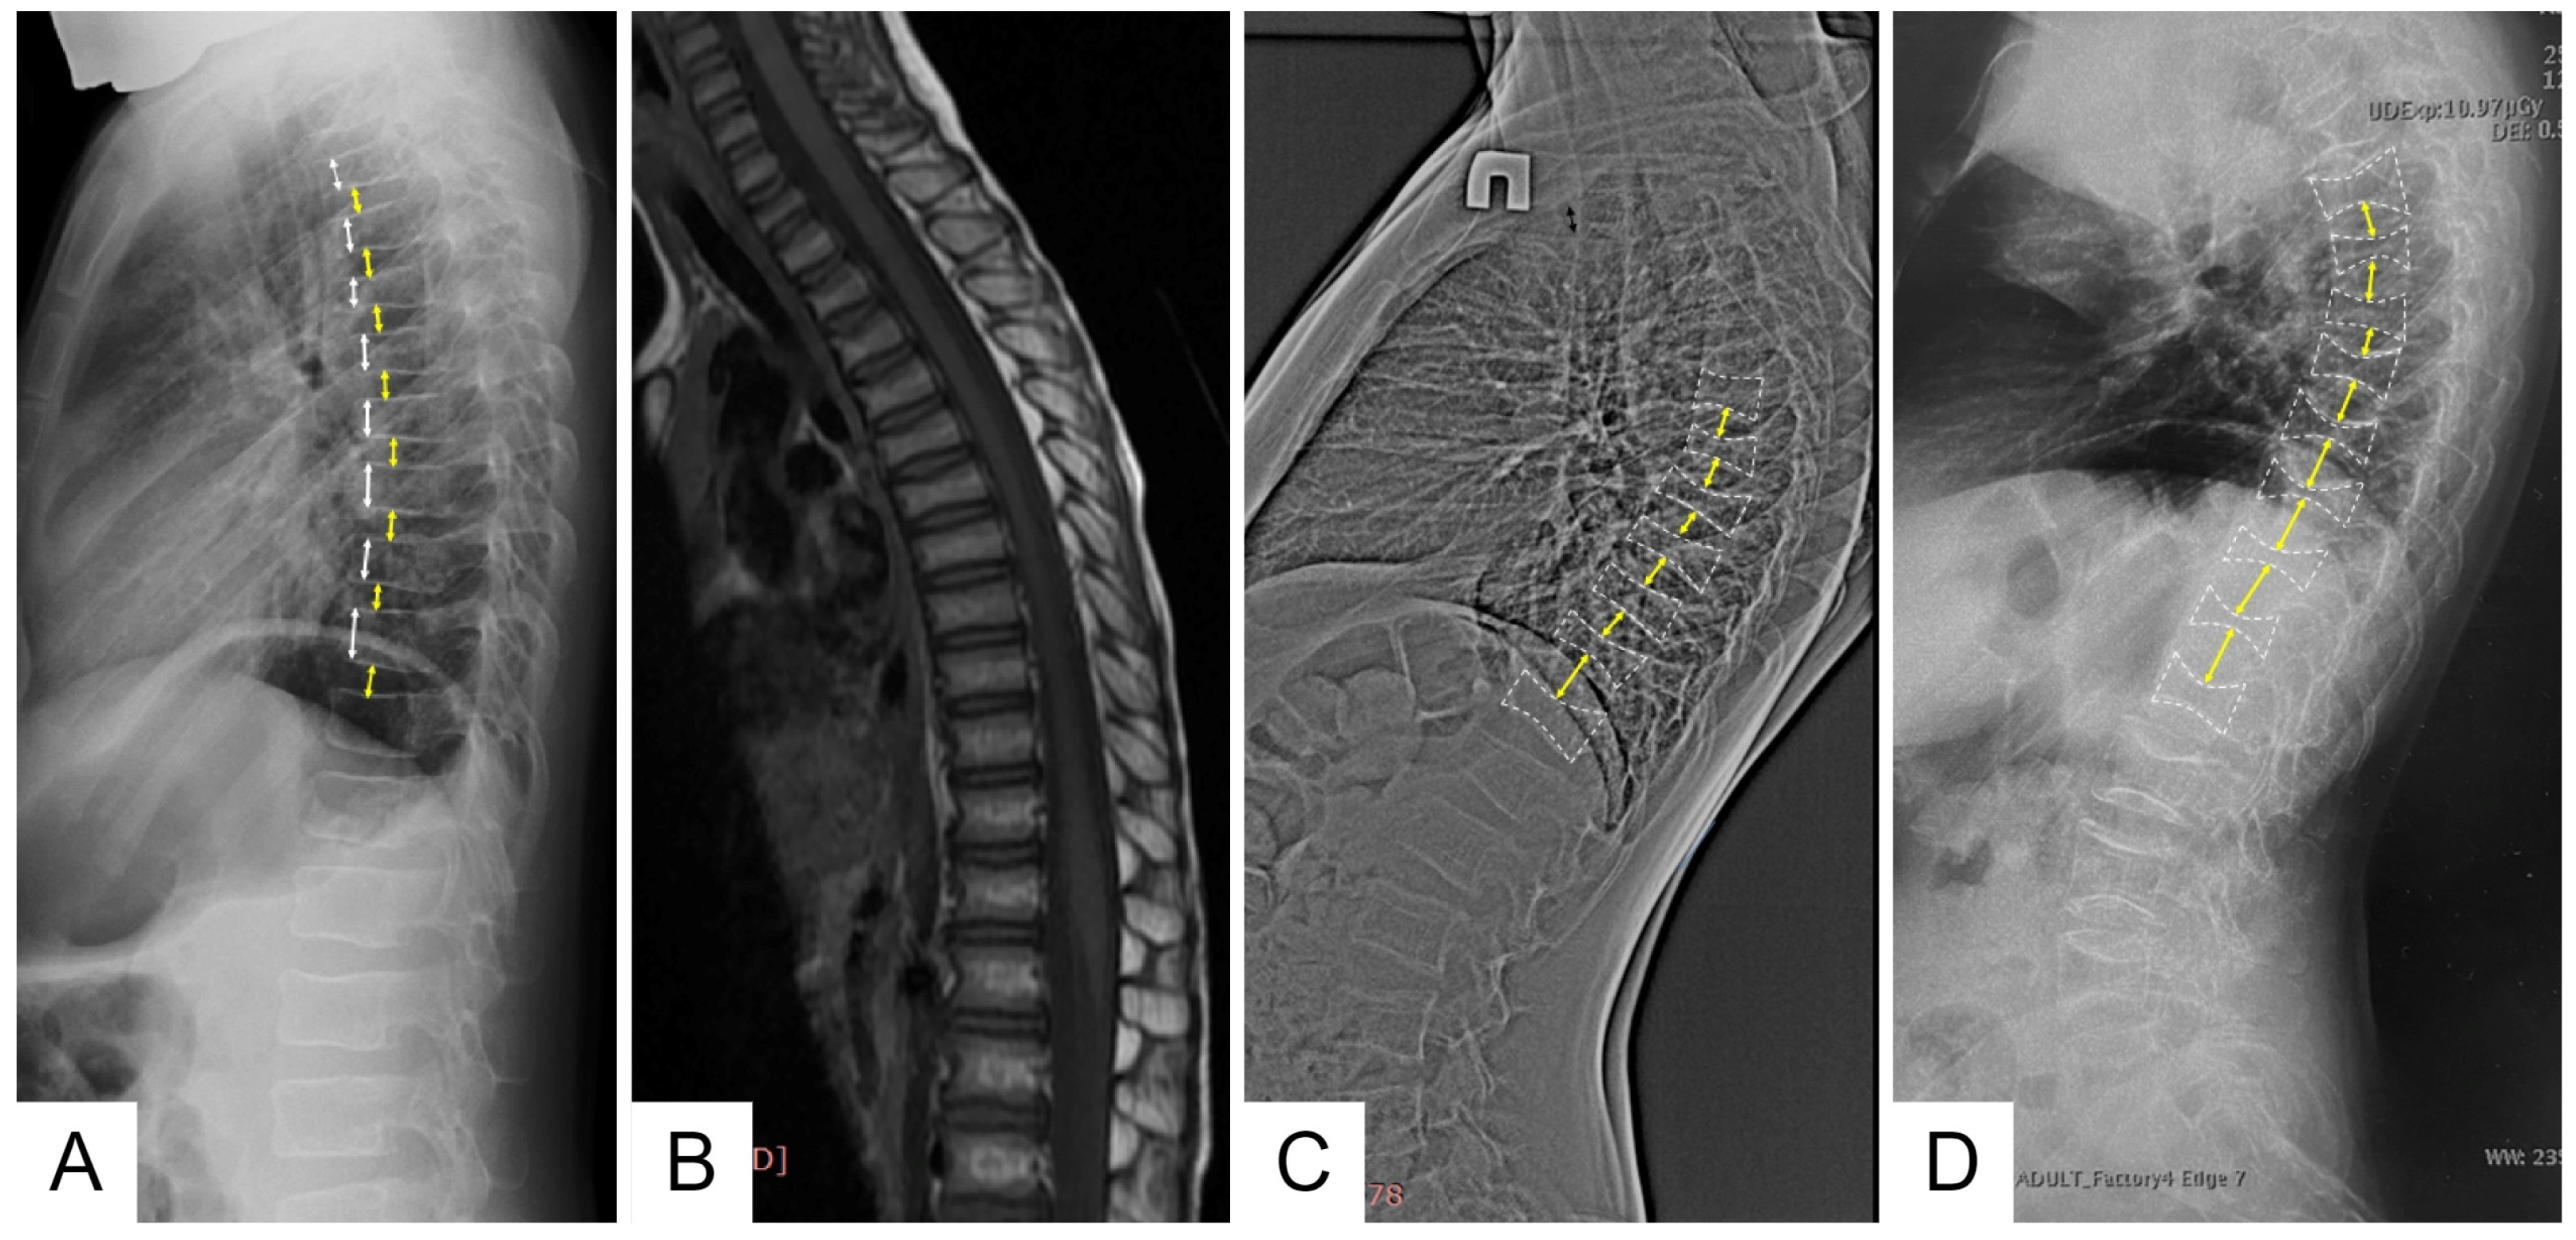

Family 1 is Belarusian and has five affected members in three generations. Proband (III-4) is a 6-year-old boy who started to complain (pointed to where it hurt) of lower back pain from the age of 1 year 7 months, according to his parents. This pain usually lasted from 2 weeks to 1 month and limited the patient’s physical activity, as he was afraid to walk the stairs. Taking into account the increasing lower back pain, an MRI of the thoracolumbar spine was performed at the age of 4 years, which revealed signs of compression fractures of the C7, Th 2-8 vertebral bodies (Figure 2).

According to the results of the X-ray densitometry performed at the age of 4 years, the BMD of the lumbar spine was 0.289 g/cm2, Z-criterion was −3.2. The laboratory study of calcium phosphate metabolism revealed an increased level of alkaline phosphatase activity and decreased level of 25-hydroxyvitamin D (25(OH)D). Laboratory tests showed the following results: ionized calcium—1.23 mmol/L (referent values: 1.03–1.23 mmol/L), alkaline phosphatase—492 U/l (referent values: 156–369), 25-hydroxyvitamin D [25(OH)D]—28 ng/ml (referent values: 30–100 ng/ml), nonorganic phosphorus—1.55 mmol/L (referent values: 1.45–1.78 mmol/L). During the patient’s observation, there was a tendency toward an increase in the pain syndrome in the back area (pain occurred during coughing, sneezing, and sudden movements), as well as a decrease in BMD values in the lumbar spine according to densitometry data (BMD = 0.259 g/cm2, Z-score: −4.2 SD), which served as a medical indication for initiating treatment with bisphosphonate-based medications (pamidronate acid at a dose of 1 mg/kg/day for 3 consecutive days, courses every 4 months). After two courses of treatment, a positive trend was observed: back pain was relieved, and BMD values increased (Table 1).

Control X-ray densitometry at the age of 6 showed positive dynamics: the BMD of the lumbar spine was 0.357 g/cm2, Z-criterion was −1.9. An X-ray examination of the spine at the age of 6 years revealed diffuse rarefaction of the bone pattern of the vertebrae and a biconcave shape of the thoracic vertebral bodies (Figure 2).

Family 2 is Russian and has four affected members in three generations. Proband (III-2) is an 11-year-old boy with severe primary osteoporosis in childhood and a history of four low-energy peripheral fractures, starting at the age of 1 year 6 months when the first fracture of the right femur occurred. Later on, at the age of 6 and 8 years, the proband sustained fractures of the wrist and foot bones, and at the age of 10 years—a fracture of both bones of the right forearm. At the age of 10 years, after active physical activity (jumping in the street), the child developed severe back pain, which an X-ray examination of the spine revealed were multiple compression fractures of the bodies of Th 3–9 vertebrae and a wedge-shaped deformity of Th 5–7, 9 vertebrae.

According to the results of the densitometry, all affected family members were diagnosed with severe osteoporosis, and an X-ray examination of the spine revealed signs of compression fractures of the vertebral bodies (Figure 2).

2.3. Family 3

Proband (II-1) is a 30-year-old woman from the Bashkirian family. The first fracture of the right femur was revealed shortly after birth, and the second fracture of the same bone was sustained at the age of 1 year. Throughout her life, multiple fractures of the upper and lower limbs (about 20) have been registered. Since the age of 17, she has been treated with bisphosphonates. At the age of 24, a corrective osteotomy of the tibia with osteosynthesis using low-profile palmar locking compression plates (LCPs) was performed. Currently, metal construction of the thighs and lower legs are installed (at the age of 25 and 26 years, respectively), and fractures of the bones of the feet occur regularly. Against the background of a break in bisphosphonate therapy, an increase in bone pain syndrome not related to physical activity is noted. At the age of 27, pamidronate acid therapy was resumed, at which point the severity of the pain syndrome was maximal, with a Z-criterion of the lumbar spine according to densitometry data of −2.4. During therapy, the patient reported a decrease in the severity of the pain syndrome and also an increase in bone mineral density at various times, with the Z-criterion ranging from 0.3 to 1.4. In addition to bisphosphonates, from November 2019 to November 2020, the patient received teriparatide in a standard dosage. After November 2021, there was a break in bisphosphonate therapy due to the coronavirus pandemic. Since the beginning of 2022, the patient has reported a recurrence of the pain syndrome, despite normal bone mineral density levels (Z = 0.8). Pamidronate acid therapy was resumed with a positive therapeutic effect. The dynamics of pain syndrome indicators and bone mineral density levels during the therapy are presented in Figure 7.

An X-ray examination of the thoracolumbar spine revealed a biconcave appearance of the vertebrae and a wedge-shaped deformity of the vertebral bodies at the entire level of the thoracolumbar spine (Figure 2). During bone scintigraphy of the skeletal system in a 30-year-old individual, no metabolically active zones were detected, which are often found in patients with osteogenesis imperfecta, even outside fracture zones and bone calluses.

Figure 2. Lateral views of the thoracic and upper lumbar spine of the patients of different ages: radiograph of the 6 y.o. boy (F1 III-4) (A)—decreased height and anterior wedging of the vertebral bodies (white arrows), increased height of intervertebral discs (black arrows); T1-weighted MRI of the same patient of the 4 y.o. (B); radiographs of the 12 y.o (F2 II-4) (C) and 30 y.o. (F3 II) (D) patients—severe platyspondyly with accentuated biconcave shape of the vertebral bodies (white dotted lines) and increased height biconvex intervertebral disks (black arrows) more prominent at the thoracic level.